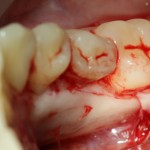

Следует учесть, что с язычной стороны слизистая оболочка более нежная и тонкая. Скелетировать альвеолярный отросток нужно с большой осторожностью:

Белой стрелочкой я отметил сосудистые пучки, входящие-выходящие в/из альвеолярного отростка. Некоторые ошибочно принимают их за нервы и этим объясняют то, что анестезия не подействовала. Напомню, что местная анестезия не действует только тогда, когда ее делают неправильно.

Черный пунктир — это примерная схема костнопластической трепанации. За последние годы я серьезно «подсел» на ультразвук — делаю им любые серьезные операции.